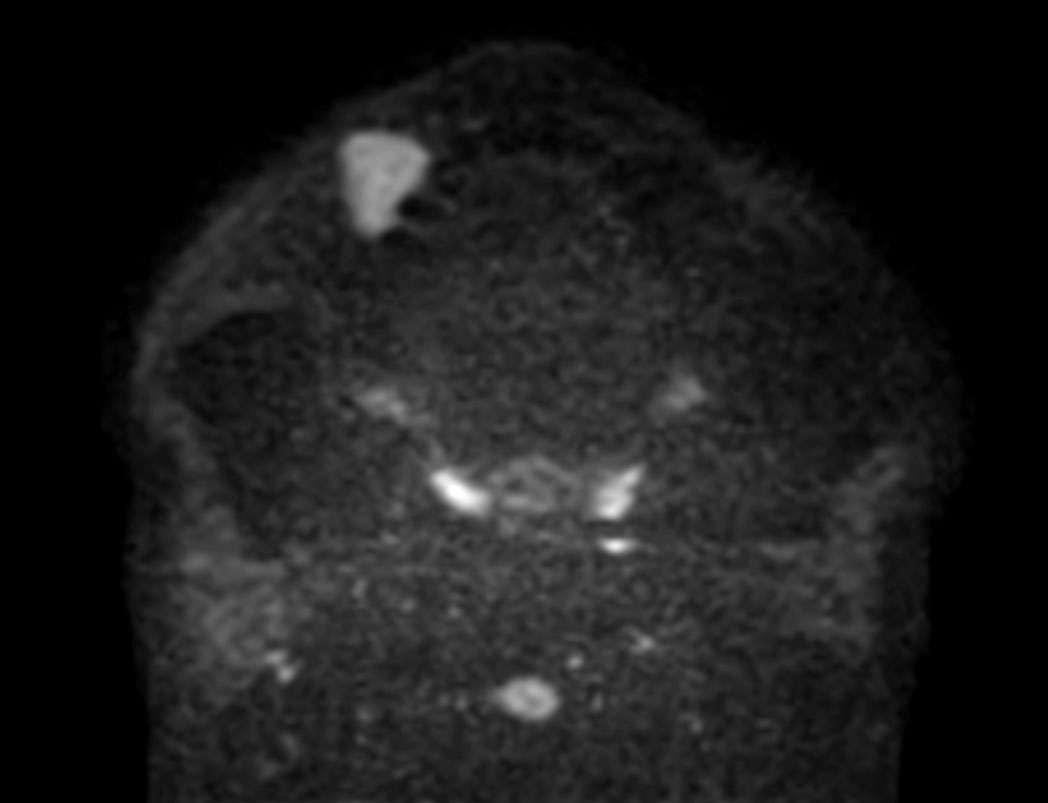

DWI TSE (ADC)